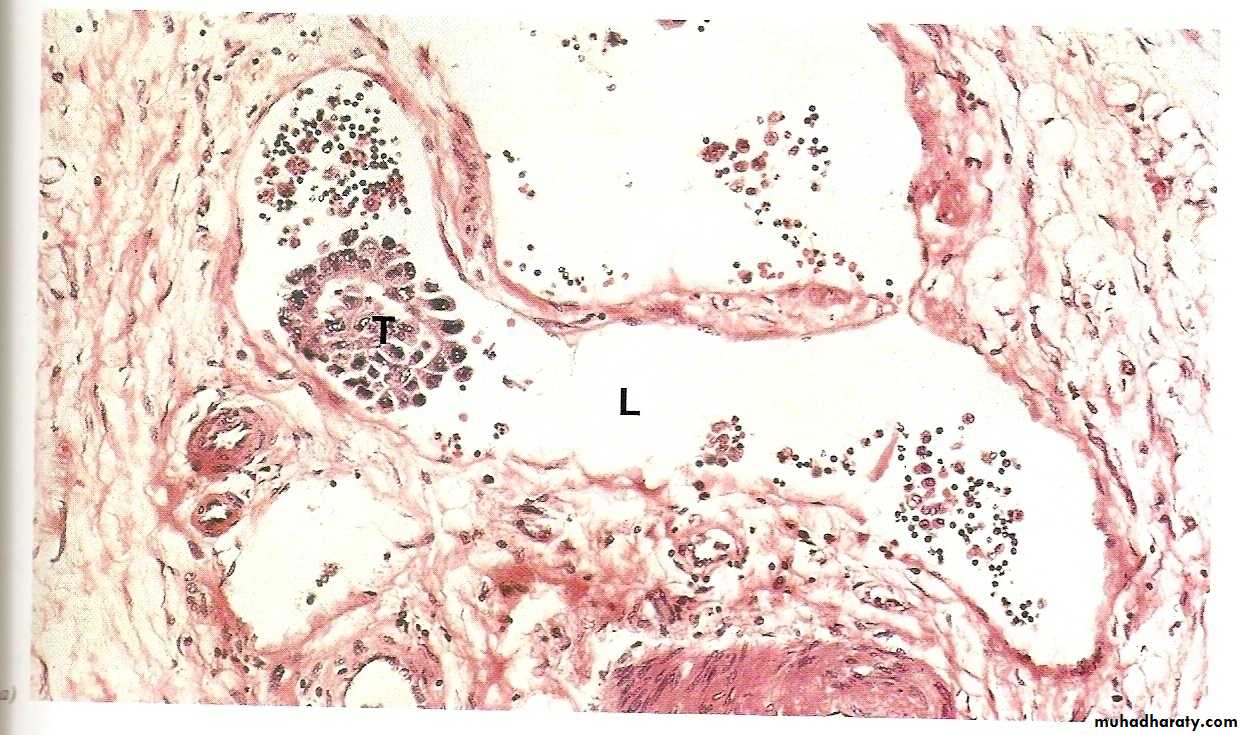

This process involves invasion of blood vessels, lymphatics and body cavities by the malignant tumor, followed by the transport and growth of secondary tumor cell masses that are discontinuous with the primary tumor. These are called secondaries.Metastasis is the absolute criterion of malignancy.

Invasion of lymphatics (lymphatic spread). This is followed by spread of the tumor to regional lymph nodes and ultimately to other sites in the body. It is common in the initial spread of carcinomas. Not all enlarged lymph nodes located at the sites of drainage of a malignancy means necessarily a metastasis. This is because immune responses to tumor antigens can result in nodal enlargement too. The latter is through the development of lymphoid hyperplasia.

Invasion of blood vessels (hematogenous spread). This is typical of all sarcomas, but is also the favored route for certain carcinomas (e.g., renal cell carcinoma). Because of their thinner walls, veins are more readily and thus more frequently invaded than arteries. Lungs and liver are the commonest site of hematogenous spread because they receive the systemic and portal venous blood respectively. Other major sites are the bones and brain.